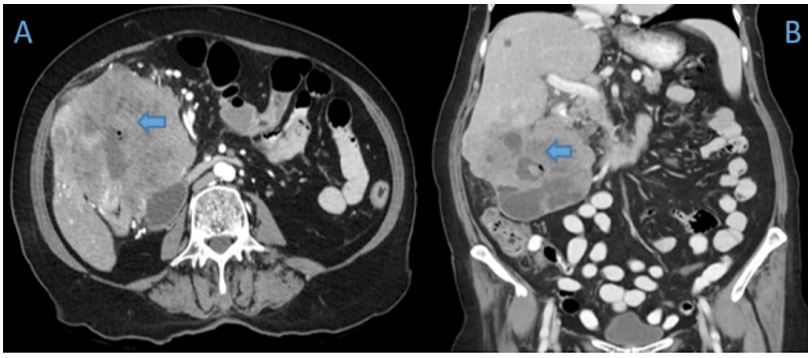

A 70-year old female was referred to the emergency department of a tertiary hospital by her general practitioner with a sixmonth history of lethargy, six-kilogram weight loss and vague right sided abdominal pain. She denied vomiting, altered bowel habit or rectal bleeding. Her relevant surgical history included cholecystectomy and thyroidectomy. There was no family history of colorectal cancer. Pertinent examination findings included a soft, non-distended abdomen with a large non-mobile palpable mass in the right upper quadrant. Her blood profile included leukocytosis (12.9 x109 /L), anaemia (Hb 79 g/L), normal bilirubin and mildly deranged liver function tests. Furthermore, she had a markedly raised CA 19.9 (5506 kU/L) and CEA (462.1 microg/L). She was admitted for a blood transfusion and further investigations. A triple phase computed tomography scan of the chest, abdomen and pelvis revealed an 11x10x10.5 cm hepatic flexure mass with invasion into the right hepatic lobe (Figure 1). Surprisingly, there was no evidence of colonic obstruction, nor distant metastatic disease. A colonoscopy demonstrated a large circumferential, fungating and partially obstructing mass extending into the ascending colon (Figure 2). Biopsy confirmed a poorly differentiated invasive adenocarcinoma (Figure 3). Following discussion at a multi-disciplinary surgical oncology meeting, she proceeded to an ileo-colonic bypass with planned adjuvant chemotherapy. Intra-operatively, the mass was invading the liver, with small amounts of ascites and no peritoneal metastasis. Proximal small and large bowel were of normal caliber. An ileo-colic side-to-side anastomosis was performed using the distal ileum and mid transverse colon. The patient made an uneventful recovery and was discharged day four post operatively with medical oncology follow up.

Figure 2: (A) Colonoscopic view of the hepatic flexure demonstrating a circumferential, fungating and partially obstructing lesion. (Blue arrow). (B) Extension into ascending colon (Blue arrow).